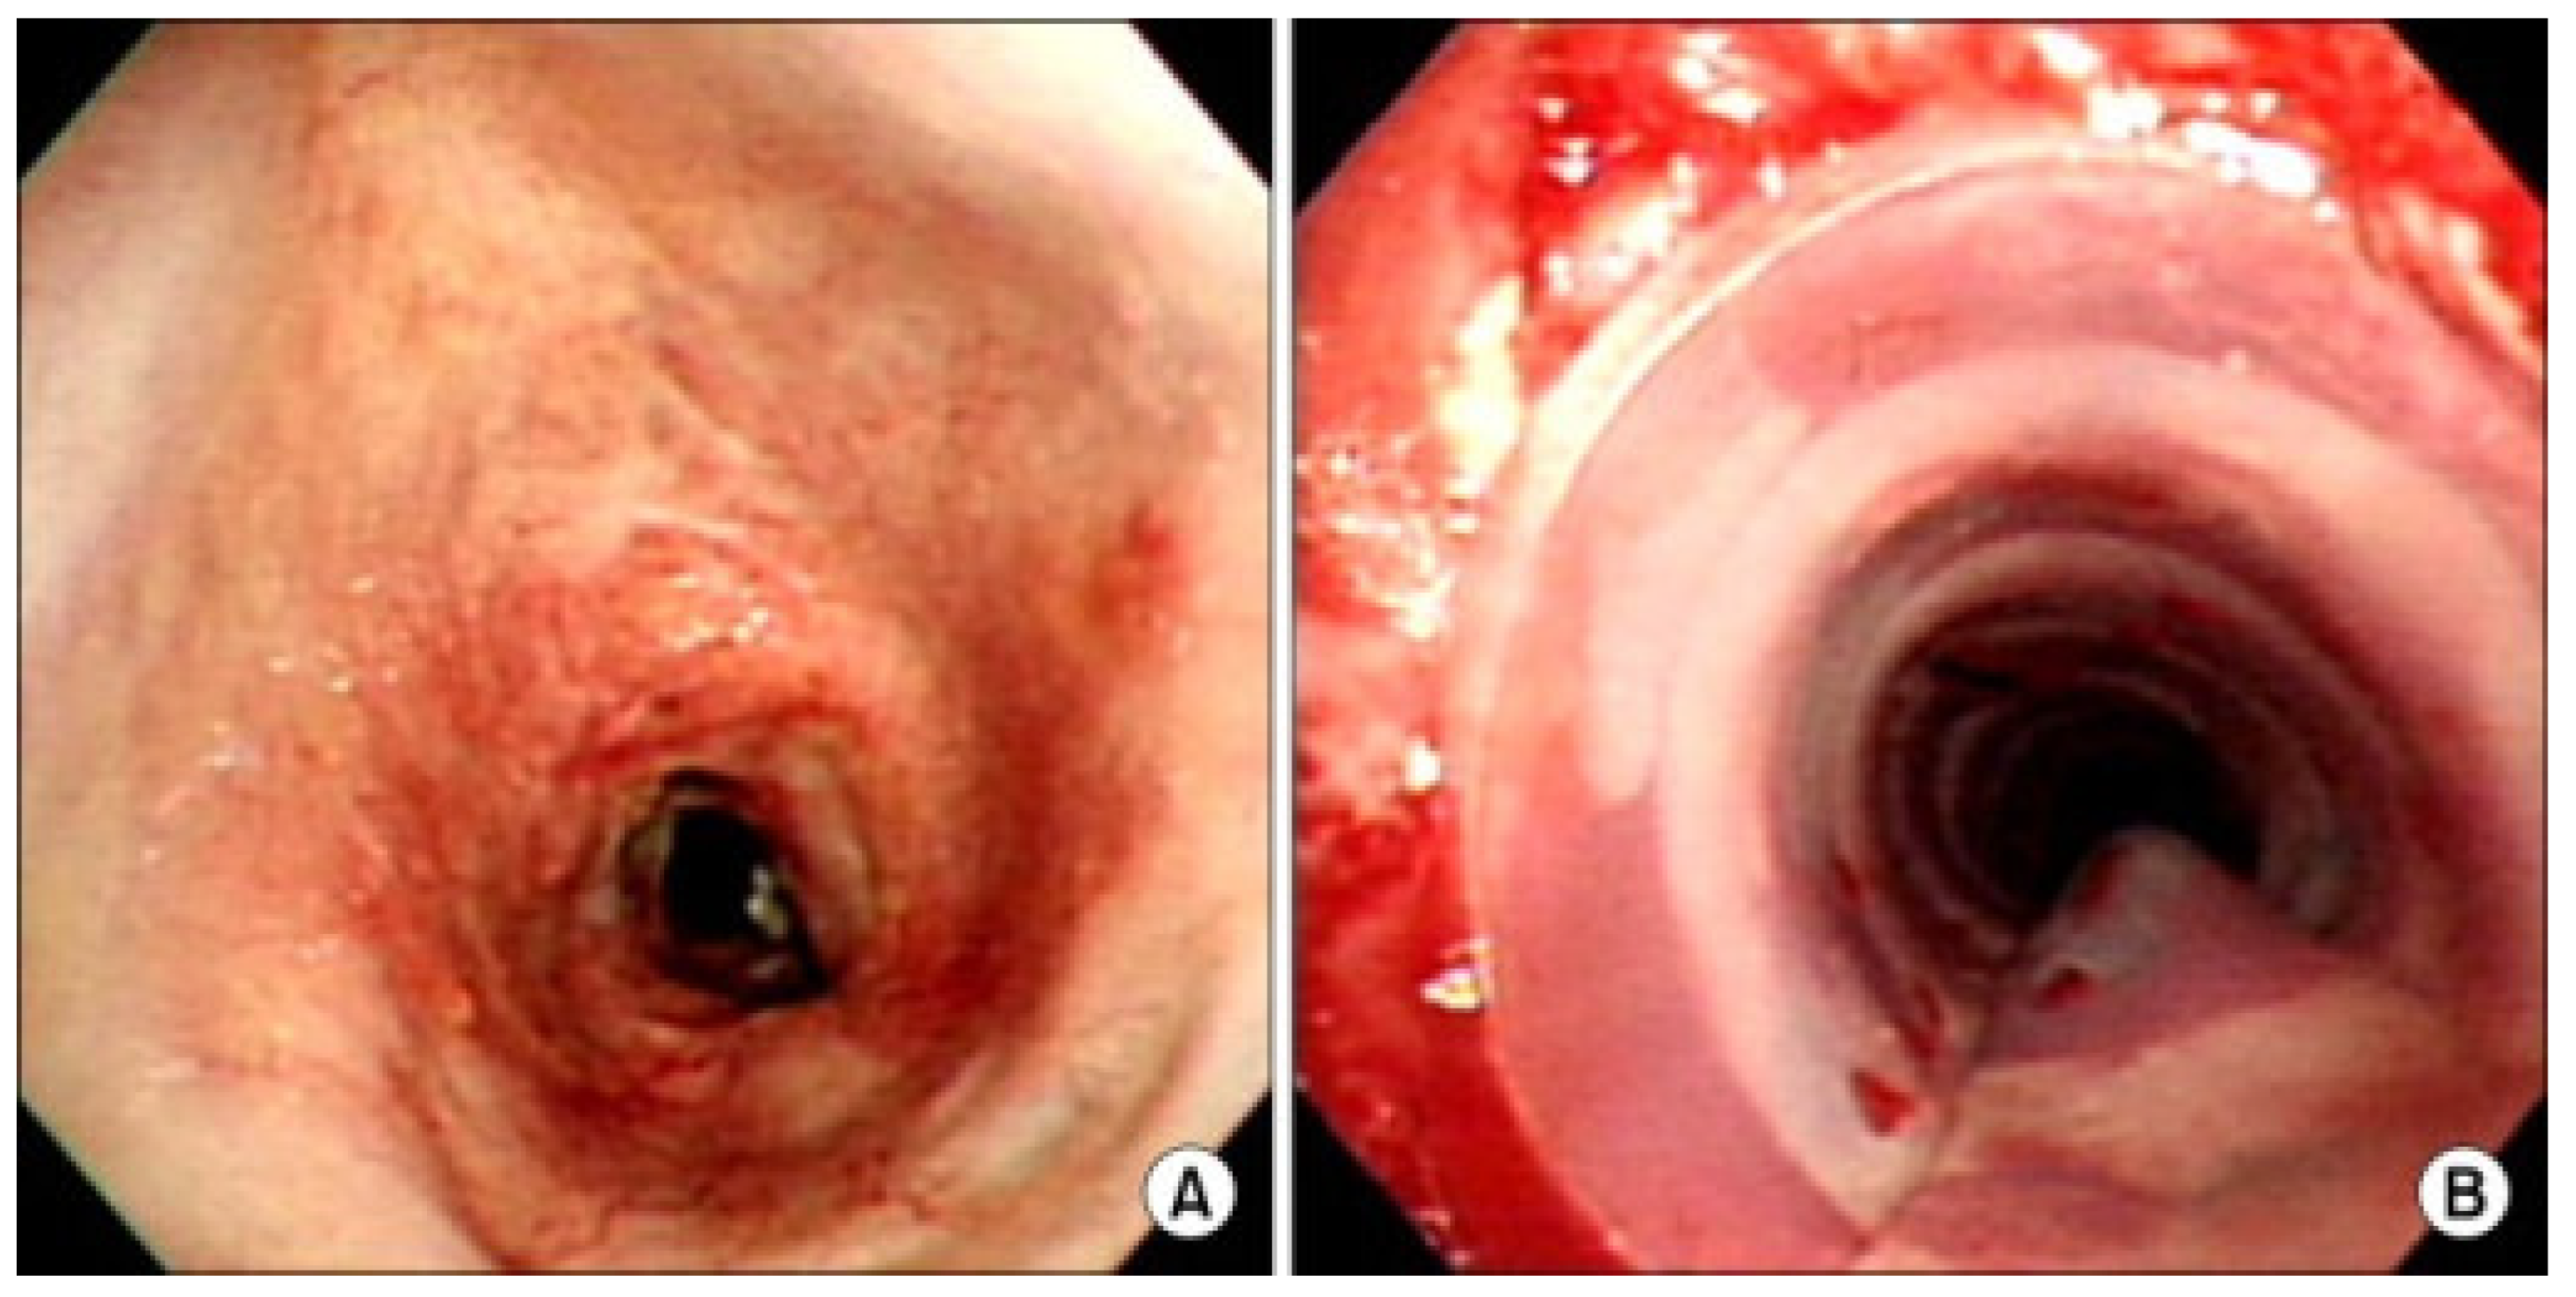

- Perryman, M.C.; Kraft, S.M.; Kavookjian, H.L. Laryngotracheal Reconstruction for Subglottic and Tracheal Stenosis. Otolaryngol. Clin. N. Am. 2023, 56, 769–778. [Google Scholar] [CrossRef] [PubMed]

- Brigger, M.T.; Boseley, M.E. Management of tracheal stenosis. Curr. Opin. Otolaryngol. Head Neck Surg. 2012, 20, 491–496. [Google Scholar] [CrossRef] [PubMed]

- Kim, H.J.; Kim, S.W.; Lee, H.Y.; Kang, H.H.; Kang, J.Y.; Kim, J.S.; Kim, M.S.; Kim, S.S.; Kim, J.W.; Yun, H.G.; et al. Clinical Experience of Rigid Bronchoscopy in Single Center. Tuberc. Respir. Dis. 2012, 72, 486–492. [Google Scholar] [CrossRef]